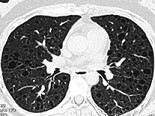

- 单项选择题女,34岁, 气喘伴呼吸困难1个月并加重,CT如图, 最可能的诊断为 ( )

A、多发性肺囊肿

B、肺淋巴管肌瘤病

C、小叶性肺气肿

D、金葡菌感染并肺气囊形成

E、支气管扩张